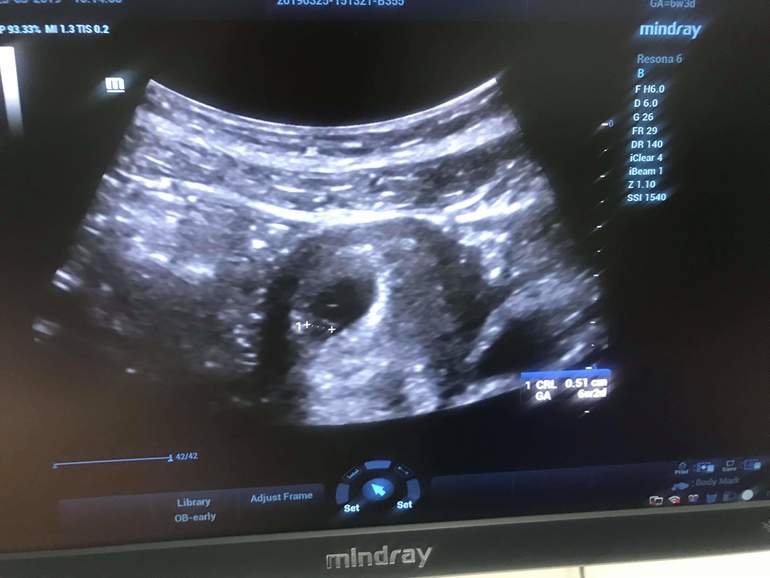

Да видела вот :)

Если я правильно понимаю то ктр 5мм и пя 16мм? Нормальные размеры для Вашего срока. У меня младший в 6+5 недель был 6,7мм, а старший сын в 7+5 недель был уже 15мм. Они быстро растут=)

Может, ПЯ 16 мм, а ктр 5? Тоже не поняла

Нет пя 5 мм, то есть эмббриончикк сам 5 мм

Не может быть чтоб пя был 5 мм и ктр 5 мм. При ПЯ 5 мм эмбриончика вообще видно не будет

Плодное яйцо 5мм

Вы путаете скорее всего что то.При ПЯ 5 мм ЭМБРИОНА ещё не видно.а 16 мм это что тогда?по вашему?я тоже больше склоняюсь что ПЯ 16 мм а эмбриончик 5 мм/тогда все в норме.Да и судить на таком сроке какой будет малыш бессмысленно.Я ростом 159-160 см детки мои все рождались 3,500 и 56 см,3,849 и 54 см,3,950 и 56 см и 3,850 и 55 см